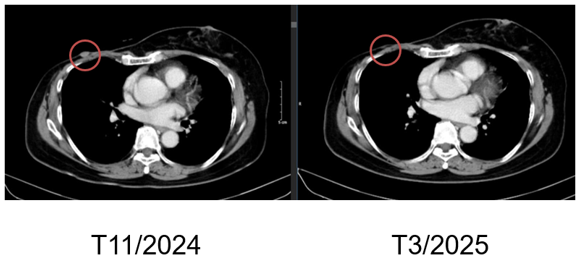

SO SÁNH TRƯỚC VÀ SAU ĐIỀU TRỊ

Hình 4. Hình ảnh chụp CT ngực trước và sau điều trị: Tổn thương tái phát thành ngực

Hình 5. Hình ảnh chụp CT ngực trước và sau điều trị: Tổn thương phổi trái

+ Thành ngực phải có nốt đặc đường kính 5mm – theo dõi tổn thương tái phát

Phổi phải: nhu mô thuỳ giữa và dưới có các khối – nốt đặc, lớn nhất 7x8mm

+ Phổi trái: nhu mô thuỳ trên và đáy phổi sát màng phổi có các khối nốt đặc, lớn nhất 9x8mm